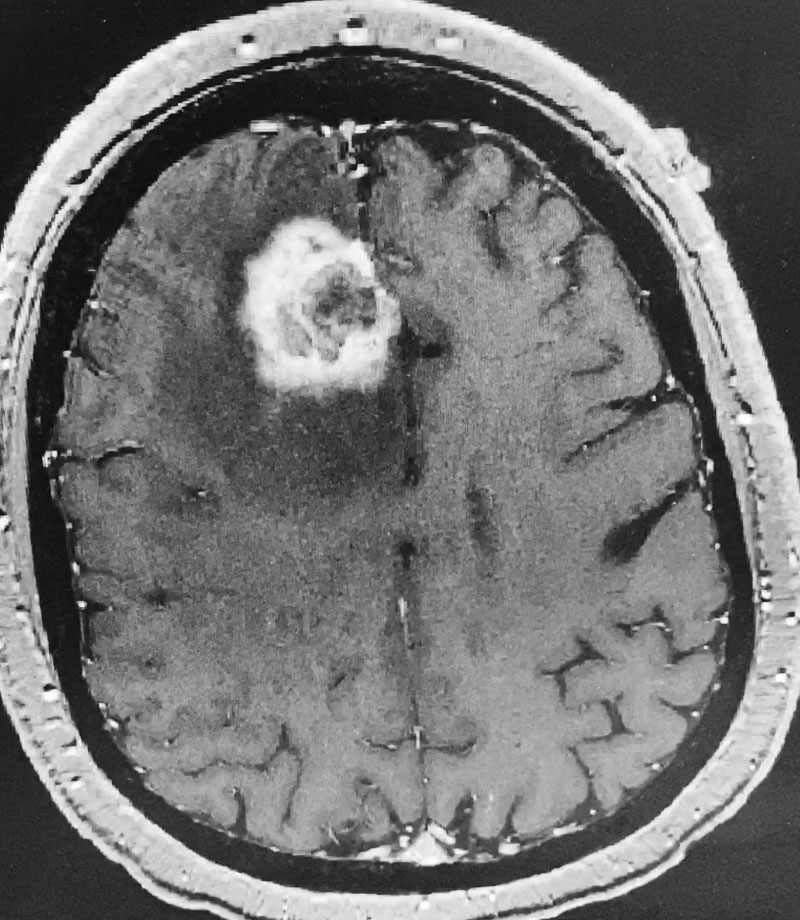

Figure 2: Axial post-contrast MRI.

The patient subsequently had increased headaches and weakness. MRI showed the mass had increased further, with persistent surrounding edema (Figure 1). Systemic work-up showed no active metastatic disease. It was suspected that there was recurrence of metastatic tumor as well as some component of necrosis (Figure 2). The patient underwent a right frontal craniotomy, by Dr. Michael Brisman, with brainlab stereotactic guidance. A cortical incision was made right over the mass. The mass was consistent primarily with metastatic tumor. The tumor was surgically removed.